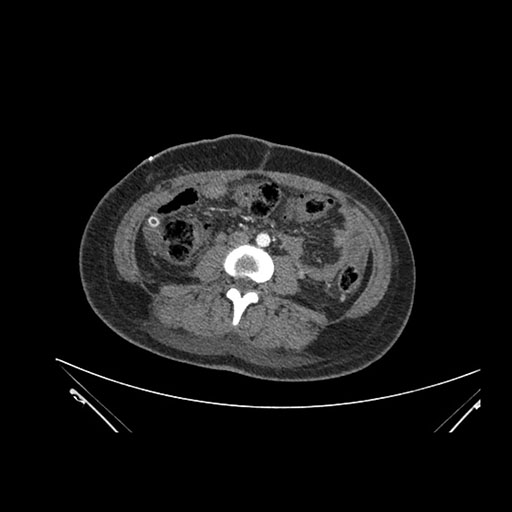

Imaging Analysis

Look through the patient's CT scan to identify any areas of concern for the necessary procedure.

Axial Arterial

Based on initial findings, which issue(s) would you be most concerned about?